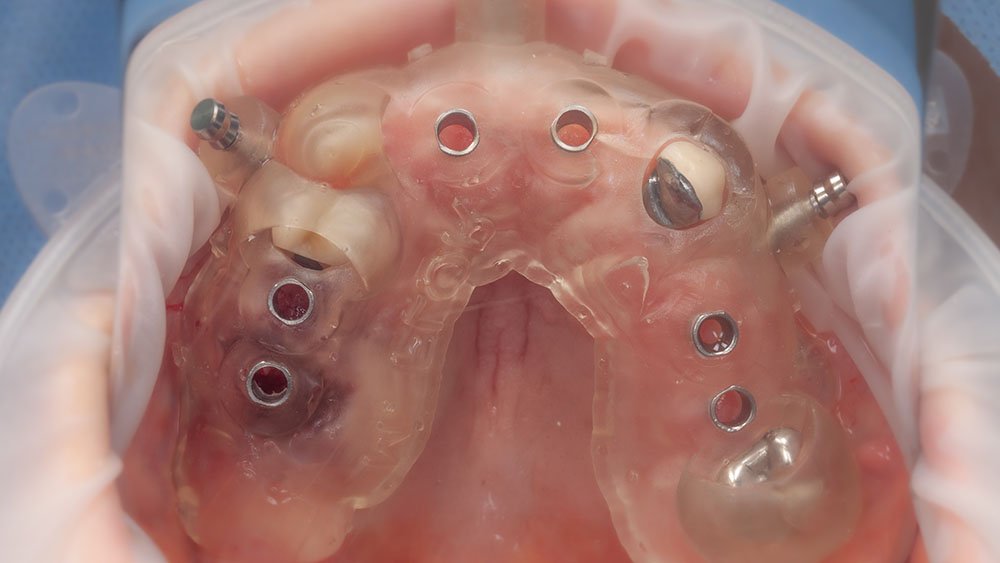

Impressão dos guias cirúrgicos superior e inferior.

Guia cirúrgico superior posicionado em boca antes das extrações dentárias.

Instalação dos implantes com o guia cirúrgico em posição.

Momento logo após a confecção dos implantes guiados superiores.